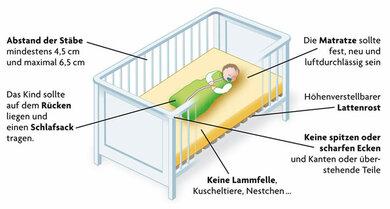

Obwohl der plötzliche Kindstod nicht mit letzter Sicherheit verhindert werden kann, gibt es Maßnahmen zur Risikominimierung. Die richtige Schlafumgebung für das Baby ist eine wirksame Präventionsmaßnahme. Dazu gehören:

– Das Baby auf den Rücken legen, um den plötzlichen Kindstod vorzubeugen

– Einen passenden Babyschlafsack verwenden und auf Decken, Kissen und Kuscheltiere verzichten

– Ein eher kühles Schlafzimmer mit einer Raumtemperatur von maximal 18 °C bieten

– Das Baby im eigenen Bett im Elternschlafzimmer oder in einem Beistellbett schlafen lassen

1. Legen Sie Ihr Baby zum Schlafen auf den Rücken und nicht auf den Bauch oder in Seitenlage.

3. Verwenden Sie einen passenden Babyschlafsack und verzichten Sie auf Decken, Kuscheltiere und Kissen.

– Ein Babyschlafsack sorgt dafür, dass das Baby keinen Hitzestau bekommt und ungehindert atmen kann.

4. Sorgen Sie für ein eher kühles Schlafzimmer, in dem Ihr Baby schläft.

– Die Raumtemperatur sollte 18 °C nicht überschreiten.

5. Legen Sie Ihr Kind in sein eigenes Babybett im Elternschlafzimmer.

– Beistellbetten sind ebenfalls eine gute Option, da sie direkt am Elternbett angebracht werden können.